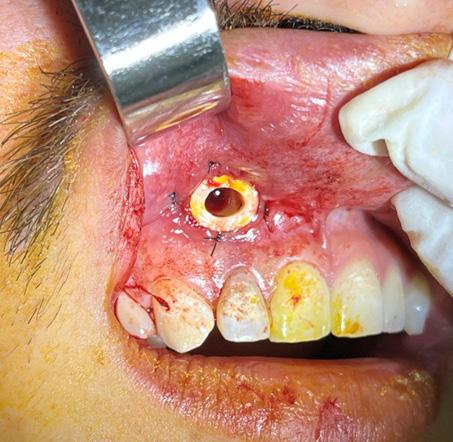

Figura 1. Cuatro formas de língulas mandibulares. Truncada (A), triangular (B), nodular (C) y asimilada (D) (8).

Figura 2. Formas de la língula en mandíbulas adultas secas. Truncada (A), presenta una forma triangular cortada en su vértice. Triangular (B), con vértice dirigido hacia el cóndilo mandibular. Nodular (C). Asimilada (D), no se evidencia la prominencia ósea lingular (8, 9).